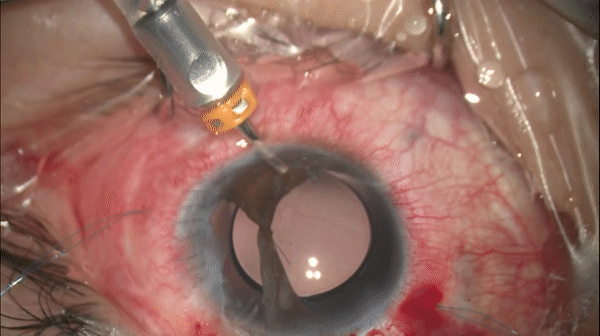

Step 8

巩膜层间缝线往复穿行

将8-0缝线从巩膜穿刺口进针,平行于角膜缘在巩膜中穿行约3.0-4.0mm后穿出,随后从穿出部位进针,从先前巩膜穿刺口穿出以完成巩膜层间往复穿行。